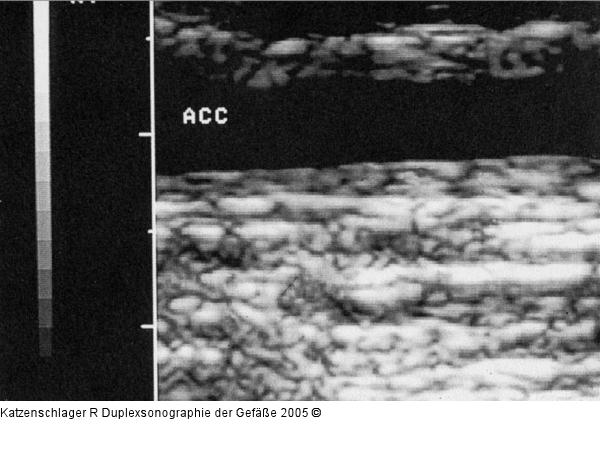

Abbildung 15: Duplexsonographie - Intima-Media Intima-Media-Verdickung bei Riesenzellarteriitis |

Intima-Media-Verdickung bei Riesenzellarteriitis |